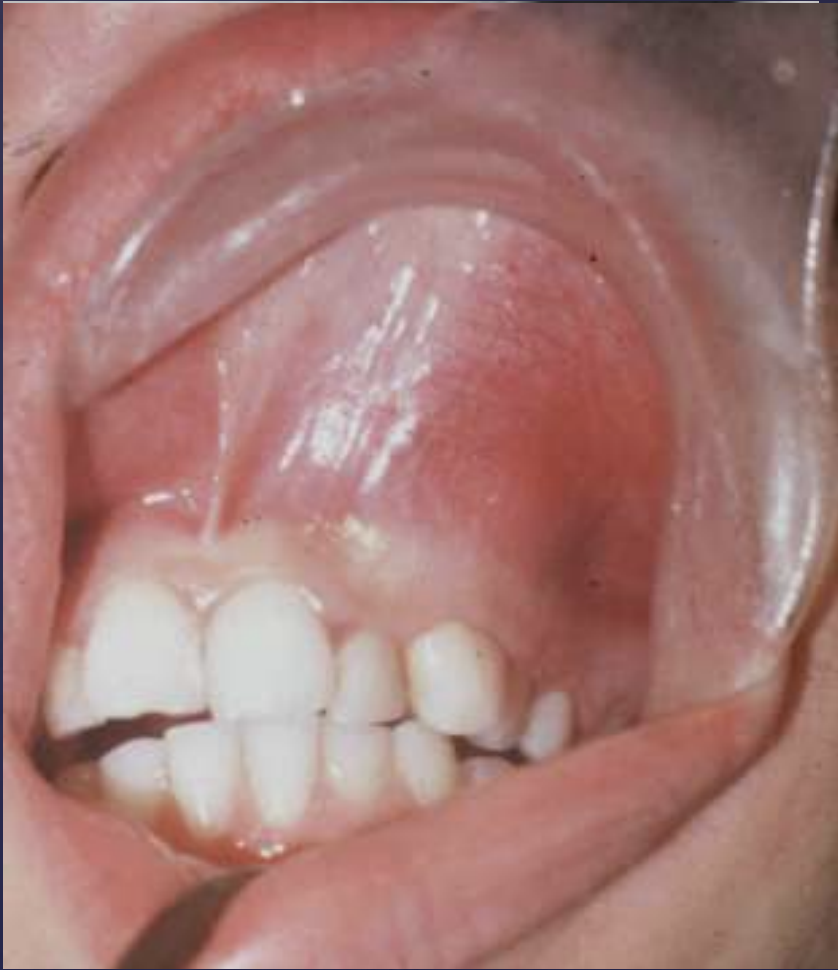

Unicystic Ameloblastomas

expansion/thinng ext. oblique ridge